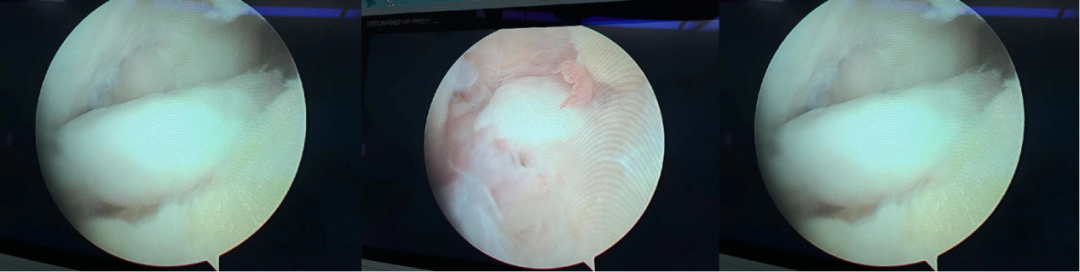

术中情况

手术不到半个小时就顺利结束,麻醉清醒后,王显勋指着盒子给余女士看:“这就让你膝关节卡住的‘罪魁祸首’。”只见盒子里装着两枚乳白色卵石样的游离体,其中一枚足有大拇指甲盖大小,另一枚也有豌豆大小。